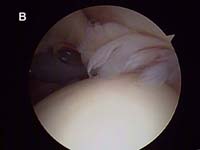

The video below is a diagnostic arthroscopy procedure as viewed from the back of the joint looking to the front. This patient has mild, partial thickness fraying at the rotator cuff insertion. This tear is analogous to the tear show in Fig. 5.

- partial-thickness or incomplete tears can occur. While these tears may progress to complete tears, rehabilitation can frequently strengthen the remaining intact cuff tissue and halt the process. Many persons with partial-thickness tears will never require surgery if they undergo an appropriate physical therapy rehabilitation to address muscle imbalances. (See Fig. 5. and video above)